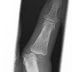

Fall 21: Blickdiagnose Die Fingerluxation

Natürlich veranlassen Sie zuerst ein Röntgen, um nicht eine Luxationsfraktur zu übersehen!   Das Röntgen bestätigt eine Luxatio...

Fall 21 Blickdiagnose: Der krumme Finger

Zur Aufnahme kommt ein älterer Heimbewohner. Er wäre aus seinem Rollstuhl auf die rechte Hand gefallen. Der Schwester wäre diese Fehls...